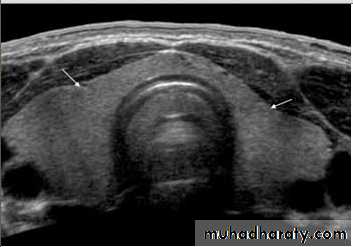

• US is the investigation of first choice.

• US with high-resolution equipment has a high sensitivity (80–90 %) for the detection of parathyroid adenoma.• US appearance of parathyroid adenoma is a well-defined hypoechoic mass usually of around 1.0–1.5 cm in diameter.

• Most parathyroid adenomas lie behind or immediately below the thyroid gland.

• The principal cause of a false-negative US is ectopic adenoma, which may be present in up to 10 % of cases; ectopic sites include mediastinum and carotid sheath.